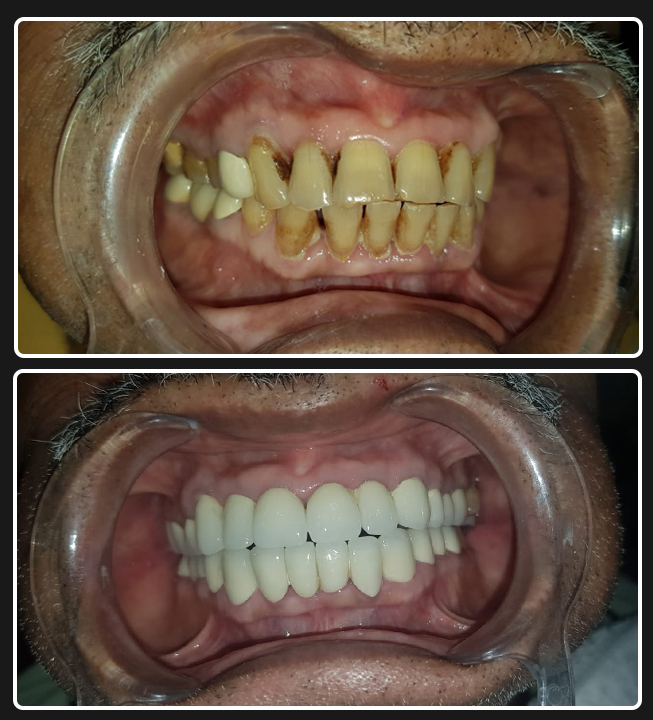

Full Mouth Implant Case

Full Mouth Implants with all Ceramic Crowns

Mr. Ramnani (Florida, USA)